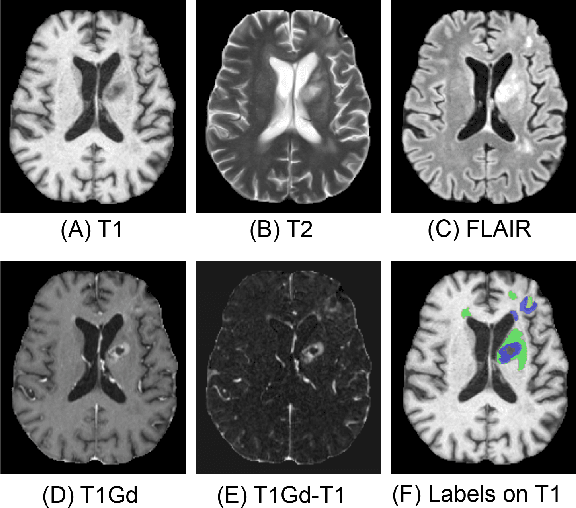

Abstract:Segmentation is a crucial task in the medical imaging field and is often an important primary step or even a prerequisite to the analysis of medical volumes. Yet treatments such as surgery complicate the accurate delineation of regions of interest. The BraTS Post-Treatment 2024 Challenge published the first public dataset for post-surgery glioma segmentation and addresses the aforementioned issue by fostering the development of automated segmentation tools for glioma in MRI data. In this effort, we propose two straightforward approaches to enhance the segmentation performances of deep learning-based methodologies. First, we incorporate an additional input based on a simple linear combination of the available MRI sequences input, which highlights enhancing tumors. Second, we employ various ensembling methods to weigh the contribution of a battery of models. Our results demonstrate that these approaches significantly improve segmentation performance compared to baseline models, underscoring the effectiveness of these simple approaches in improving medical image segmentation tasks.